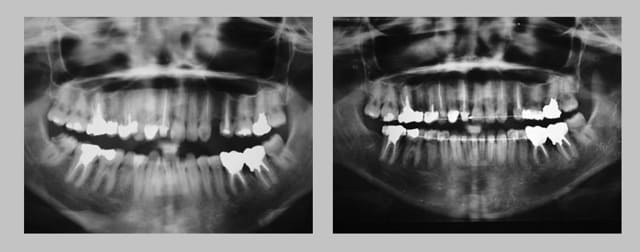

voici les pano avant, apres

Pano 1 evrdon - Eugenol